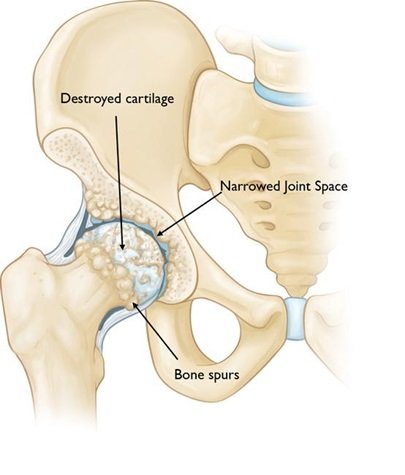

In a total hip replacement (also called total hip arthroplasty), the damaged bone and cartilage is removed and replaced with prosthetic components.

• 1. The damaged femoral head is removed and replaced with a metal stem that is placed into the hollow center of the femur. The femoral stem may be either cemented or “press fit” into the bone.

• 2. A metal or ceramic ball is placed on the upper part of the stem. This ball replaces the damaged femoral head that was removed.

• 3. The damaged cartilage surface of the socket (acetabulum) is removed and replaced with a metal socket. Screws or cement are sometimes used to hold the socket in place.

• 4.A plastic, ceramic, or metal spacer is inserted between the new ball and the socket to allow for a smooth gliding surface.